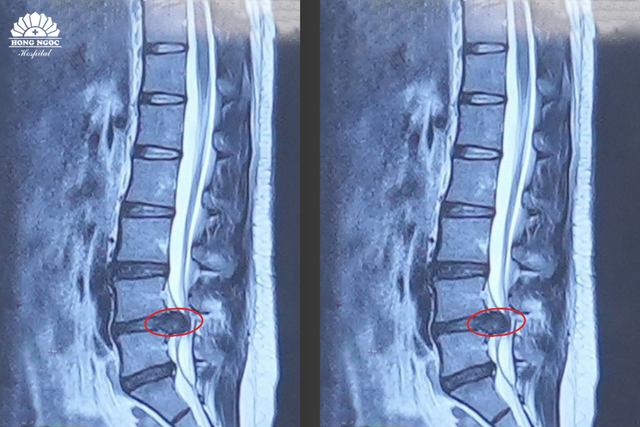

Sau khi tìm hiểu kỹ, chị L đã lựa chọn đến Bệnh viện Hồng Ngọc thăm khám cùng PGS.TS.BS Hà Kim Trung. Kết quả chụp cộng hưởng từ (MRI) cho thấy chị bị thoát vị đĩa đệm L4/5, khối thoát vị chèn ép rễ thần kinh bên phải. Đây là nguyên nhân chính gây tình trạng đau, tê và yếu chi dưới.

Khối thoát vị chèn ép gây hẹp ống sống qua phim chụp cộng hưởng từ (MRI)

Theo PGS.TS.BS Hà Kim Trung (Chuyên gia phẫu thuật thần kinh, cột sống – BVĐK Hồng Ngọc) cho biết: "Thoát vị đĩa đệm cột sống thắt lưng đang có xu hướng trẻ hóa, do thói quen ngồi lâu một chỗ, ít vận động và tư thế làm việc sai,… làm tăng nguy cơ mắc bệnh. BN này được chẩn đoán thoát vị đĩa đệm cột sống thắt lưng L4/5 gây chèn ép rễ thần kinh và hẹp ống sống, dẫn đến biến chứng rối loạn cảm giác, giảm vận động rõ rệt. Với người trẻ đang trong độ tuổi lao động, giải pháp tối ưu là phẫu thuật giải phóng chèn ép, kết hợp hàn xương và nẹp vít cố định cột sống. Đặc biệt, phẫu thuật tại vị trí L4/L5 không gây liệt do đốt sống không có tủy, giúp chấm dứt tình trạng tê buốt, phục hồi khả năng vận động, duy trì độ vững cột sống và thực hiện các động tác cúi, gập, xoay khi lao động bình thường, đồng thời hạn chế nguy cơ tái phát lâu dài".